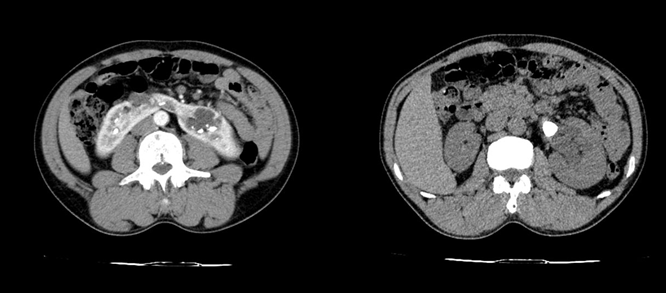

BN nam 46 tuổi tiền sử phát hiện sỏi thận cách 6 tháng chỉ điều trị nội khoa, vào viện ngày 3/5 do đau hông lưng bên T đau lan ra sau lưng, tiểu dắt buốt nhiều ngày. Đã đi khám nhiều nơi với mong muốn được phẫu thuật. BN vào viện được làm các xét nghiệm cơ bản, CDHA chụp CLVT có hình ảnh ứ nước thận T, sỏi thận T 01 viên bể thận KT 22×1.5mm ,01 viên đài dưới 12 x 18mm, trên thận móng ngựa.

Hình 1 Hình ảnh thận móng ngựa và vị trí sỏi trên CLVT

Ở BN này đều có sỏi rải rác ở 2 bên thận tiên lượng lấy sạch sỏi là rất khó khăn , sỏi gây giãn thận chủ yếu nằm ở bên T triệu chứng cũng điển hình bên T nhìn vào CLVT bể thận T xoay trước tuy nhiên vẫn có đường vào bể thận đài giữa. Sau khi hội chẩn các bác sỹ trong khoa chọn PP tán sỏi qua da cho BN.